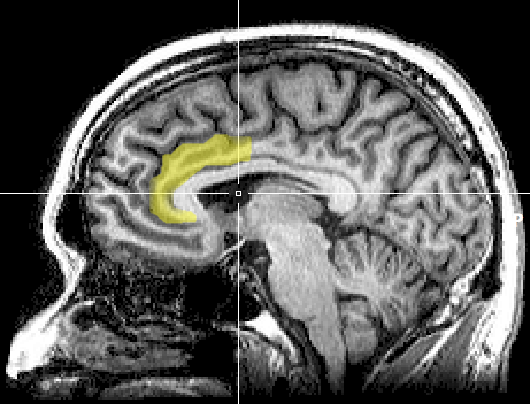

这个系统的核心枢纽叫前中扣带皮层 AMCC

AMCC(前中扣带皮层)就像大脑里的一个“指挥中心”,负责评估一件事值不值得我们花力气去做。它会权衡我们需要消耗的能量和可能得到的回报,帮助我们决定要不要行动。

AMCC:动机、奖赏与生理反应的交汇处

它像迎难而上的总开关:被激活时,机体会自动进入前倾状态,心血管、内分泌和注意网络一并调高,主观感受是挑战在即,我要迎上去

当它低活性时,同样的外界要求更像威胁,行为倾向自然转向躲避与拖延。

AMCC不是单打独斗,它位于多条通路的交汇处:

一端连着奖赏与动机系统,决定你是否愿意朝目标靠近;

一端连着自主神经系统,决定你在压力下是兴奋有序还是紊乱崩溃;

还接入预测与误差监控网络,实时评估“我能不能应付眼前这一下”。

因此,能否扛事,本质是这套评估与动员机制能不能顺利点火